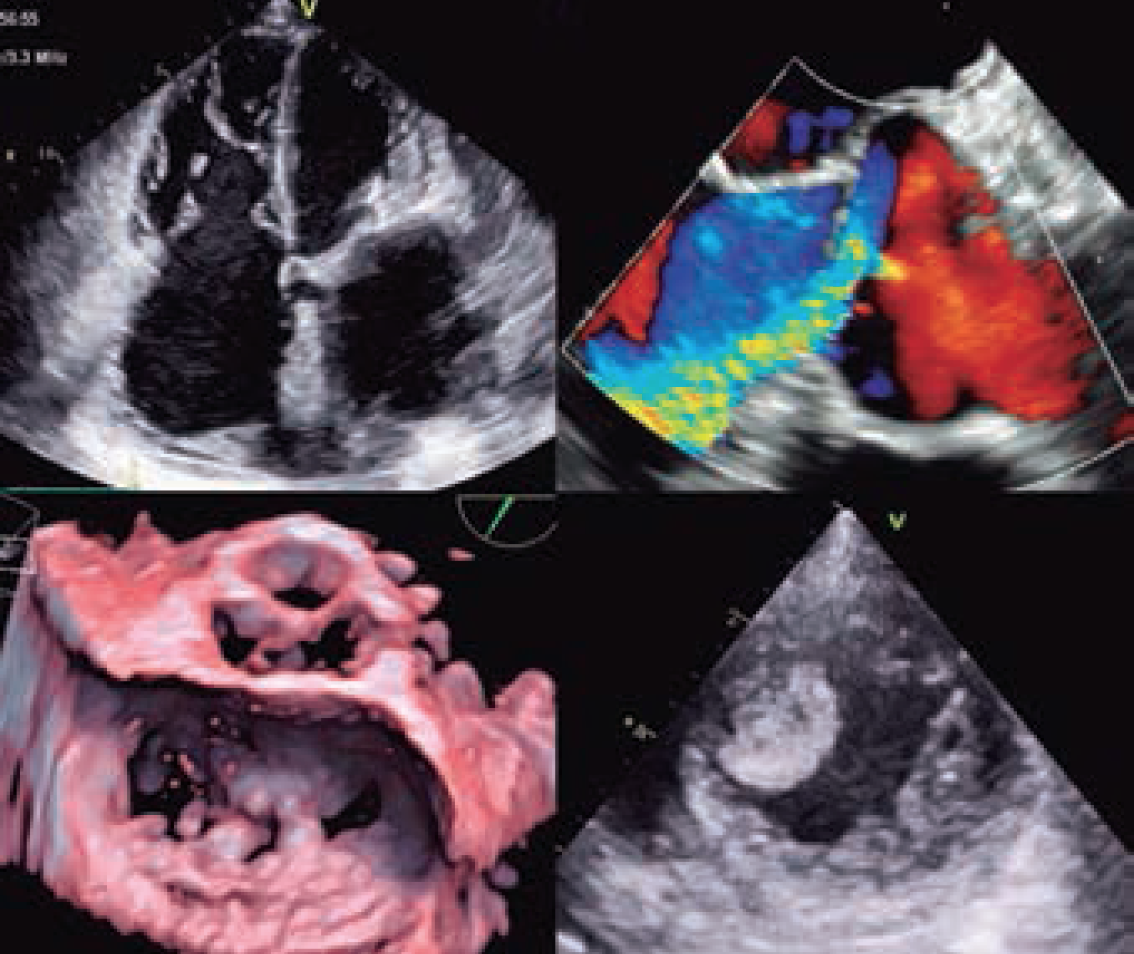

XVII Curso teórico-práctico de ecocardiografía

Dirigido a : Cardiología, Medicina Intensiva, Anestesia y Reanimación, Neurología